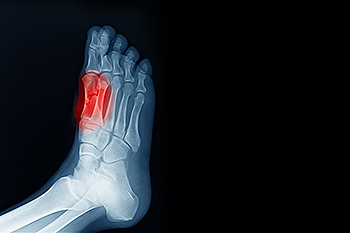

For more serious cases in which the toes have become inflexible and rigid, surgery may be suggested. During the operation, the toe would receive an incision to relieve pressure on the tendons. A re-alignment of the tendons may then be performed by removing small pieces of bone to straighten the toe. In some cases, the insertion of pins is needed to keep the bones in the proper position as the toe heals. The patient is usually allowed to return home on the same day as the surgery.